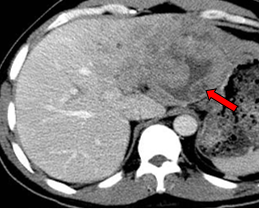

影像学检查:

2011-01-06我院上腹部CT:

肝左叶巨块型肝癌(13.8cm×9.1cm),伴肝右后叶子灶,门静脉左支、肝左静脉及下腔静脉内癌栓。